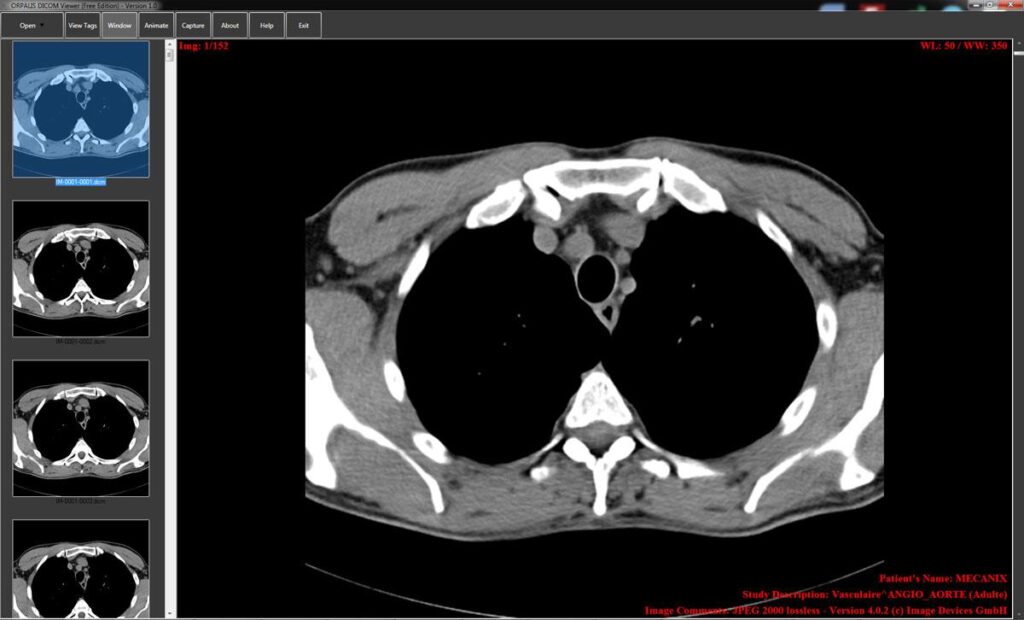

DICOM viewers have more than simple image display functions. They understand embedded metadata and visual data. This is because window leveling assists in contrast optimization to diagnose properly. There is zoom and pan functionality.

Multi-series and multi-frame navigation facilitates complicated research. Anatomical measurements are evaluated with the help of measurement tools. Clinical reporting is facilitated by the use of annotation features. There is the support of modality; it consists of CT, MRI, ultrasound, and X-ray.

Diagnostic reliability has a direct relationship with performance. The viewers are required to manipulate massive DICOM files in real-time. The accuracy rendering method maintains pixel accuracy and spatial resolution.

By providing high-bit-depth, the grayscale representation is correct. Image editing is enhanced by the use of a GPU. Form Hairs Consistency cross-platform compatible interfaces. Stability aids against crashing during important reviewing.

There is efficient caching, which enhances load times. Image reconstruction should not be unfaithful tothe initial scans. Clinical interpretation is made possible through accurate visualization. The performance-oriented viewers increase trust and diagnostic consistency.